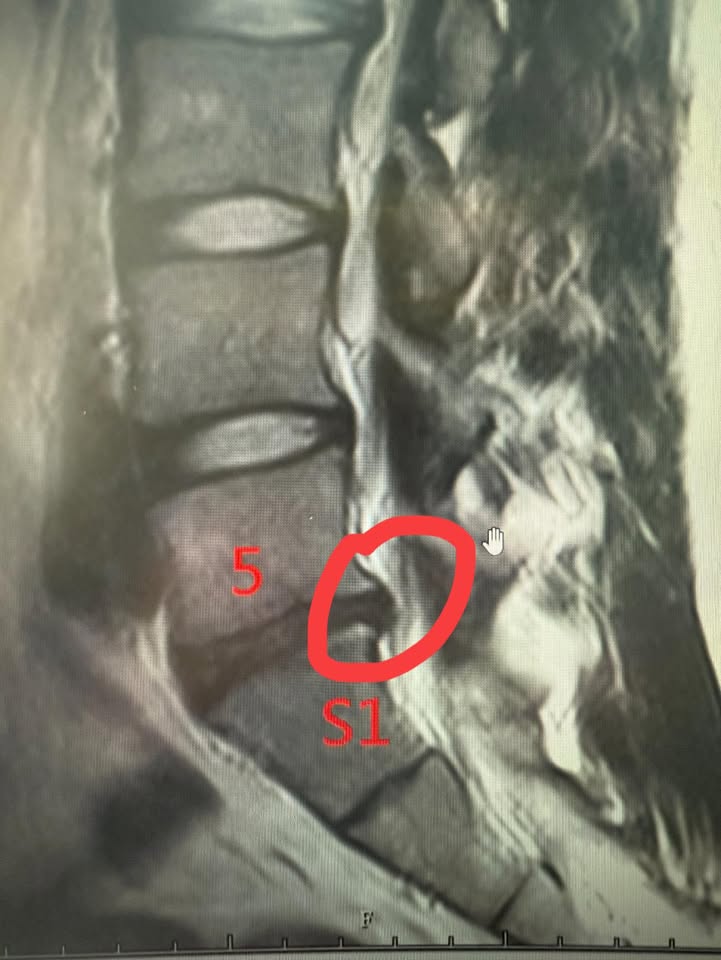

Cervical Spine Treatment Cases 精彩回顧 患者高爾夫球影片親自見證 2025.01.17 椎管狹窄曾經很難很難的病也有一線曙光 2025.01.19 2025.01.20 27歲陳小姐的巨大椎間盤突出康復之路 2025.01.23 2025.01.30 嚴重腰椎滑脫與椎管狹窄的重生之路 2025.02.05 嚴重心悸伴隨視力模糊跟血壓飆升 2025.02.07 頸椎脊髓壓迫導致手麻跛行掰咖 2025.02.11 椎間盤突出合併椎管狹窄的奇蹟之旅 2025.02.12 巨大椎間盤突出治療醫案 2025.02.13 擺脫腰痛束縛原來是椎間盤突出 2025.02.18 L小姐的交感神經症候群從痛苦折磨到重生 2025.02.19 半年無法站立原來是椎間盤巨大突出 2025.02.21 2025.02.23 2025.02.25 ← 上一頁 28 29 30 31 下一頁 →